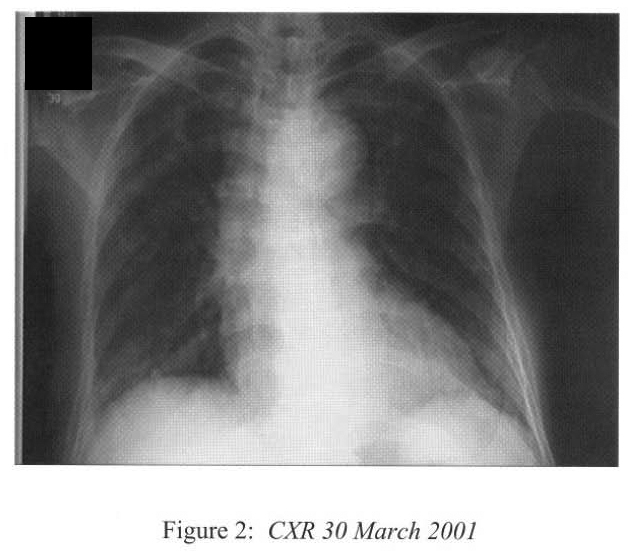

One day later she became hypotensive. There has been no change in her steroid doses and she remained afebrile. Peritoneal dialysis was withheld and intravenous fluid replaced. She passed tarry stool and this was supported with transfusion. The hypotension persisted and she eventually required inotropes infusion (dopamine and dobutamine) for blood pressure support. Her general state deteriorated with lethargy, vomiting and anorexia. She was further supported with parenteral nutritional. Dyspnoea recurred during this period of time. CXR showed diffuse bronchopneumonia in addition to the persistent right lower zone consolidation. (Figure 2) The creatinine level rose up to 912 umol/L.